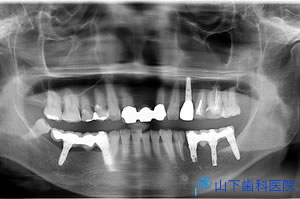

歯科治療のため撮影したオルソパントモレントゲン像で、後方の上顎結節部に長いインプラント体を埋入できる骨が有り、サイナスリフトを避けることができると判断、CT撮影して、画像データの解析、バーチャルなシミュレーション埋入手術から埋入外科用ガイドと、そのガイドからあらかじめ仮の上部構造体を作製、埋入してすぐに仮の上部構造体を装着する「ノーベルガイド」システムによる即時負荷を計画しました。

| そのオルソパントモレントゲン像です。 順調にいけば、およそ4か月でインプラント体が骨と結合します。仮の上部構造体で分かった注意点、改善点を盛り込み、よりしっかりした材質で機能的にも審美的にも満足のいく最終上部構造体を作り直す、これが大型のインプラント修復の標準治療の流れです。 |